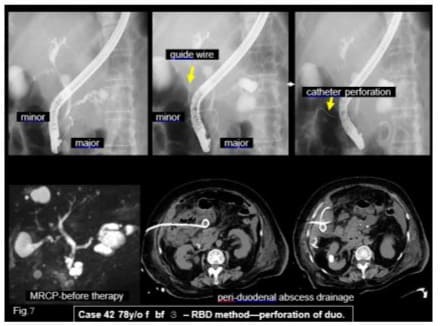

- Reverse Balloon Dilation Method: duodenal wall perfora-tion case 78 y/o f bf 3. When the catheter, proceeded into the duodenum lumen via the minor papilla under the guidewire, injury of the duodenal wall at the opposite side and made peri-duodenal abscess. Percutaneous drainage was performed, then cured. In this method, deep guidewire insertion into the duodenum via the minor papilla is necessary to prevent duodenal wall perforation by catheter (Figure 7).